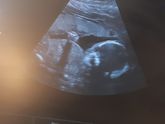

18 мая 2019 00:59 Помогите разобраться пожалуйста. Где вторая ручка...возле животика или на лице. Спасиб))